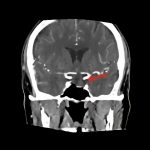

断層撮影